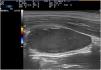

Given the diagnostic doubt, the patient underwent skin ultrasound with a 15–18–MHz linear probe (Esaote MyLab), which revealed the presence beneath the sternocleidomastoid muscle of a hypoechoic, oval structure (2.8 × 1.5 × 1.4 cm) with well-defined margins and a major axis in the longitudinal direction. Color Doppler mode showed an absence of intralesional vascularization and the presence of peripheral vascularization (Figs. 2 and 3). The ultrasound findings were compatible with an intramuscular hematoma.

In the present case, the ultrasound differential diagnosis included lipoma, lymphadenopathy, and thrombosis. Lipomas show variable echogenicity and in some cases a characteristic hyperechogenic band. They tend to be located in the subcutaneous cellular tissue and have poorly defined margins. Lymphadenopathy is usually characterized by oval morphology with a hyperechoic center and a peripheral hypoechogenic halo. In the presence of inflammation an increase in volume and vascularization may be observed, although the general morphological and structural ultrasound features are retained. Thrombosis lesions are usually hyperechogenic, are located inside the vessels, and may present peripheral vascularization (recanalization). On ultrasound hematoma appears as a hypoechoic or anechoic structure, with no internal blood flow, although Doppler mode reveals peripheral vascularization,6 as occurred in the present case.